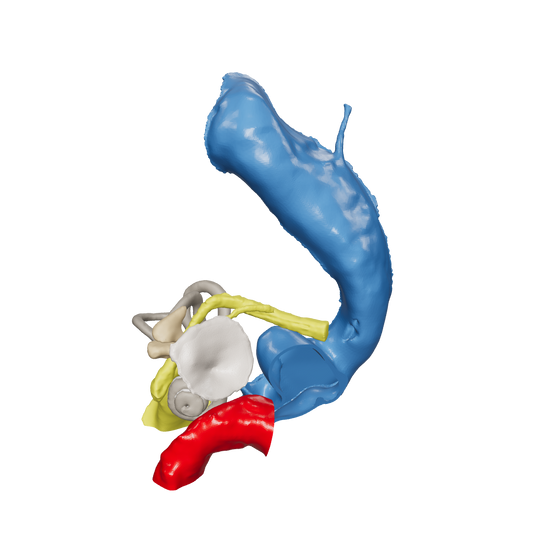

Dissect each one to learn human temporal bone anatomy, hearing and vestibular systems.

*High Contrast Colors* 3D Temporal Bones to Introduce Anatomy (6-pack)

Regular price $402.00 USDRegular priceUnit price per -